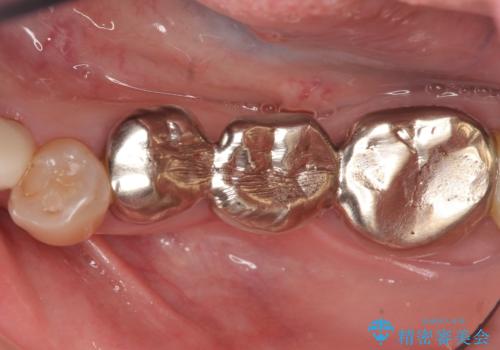

下顎は左側 4 番目から右側 4 番目までの 8 歯と左下 567 ブリッジをオールセラミッククラウンで補綴し、右下67の銀歯はセラミックインレーによる修復を行いました。

- オールセラミッククラウン…¥100,000×19、仮歯…¥10,000×19、ファイバーコア…¥20,000×6、セラミックインレー…¥70,000×2費用は治療当時の料金となります